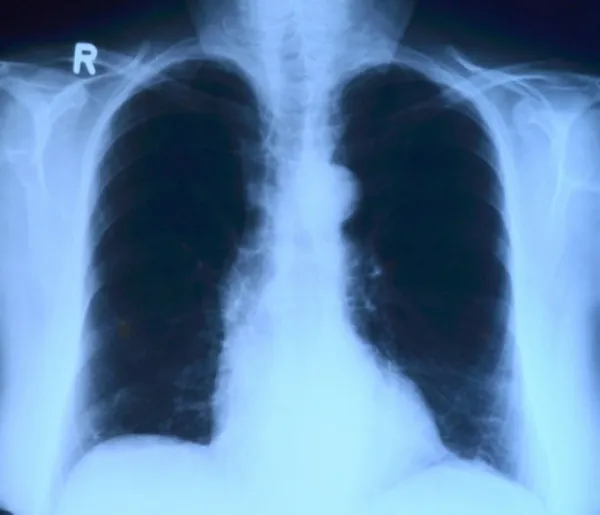

Третий комплекс располагается рядом с Тольяттинской городской поликлиникой № 2. В этих учреждениях рентгенографические исследования проводят с очень высокой точностью. На снимках видны изменения в легких, поэтому повторная диагностика с использованием компьютерного томографа не требуется. Достаточно будет сделать повторный рентген.

Фото: pixabay.com